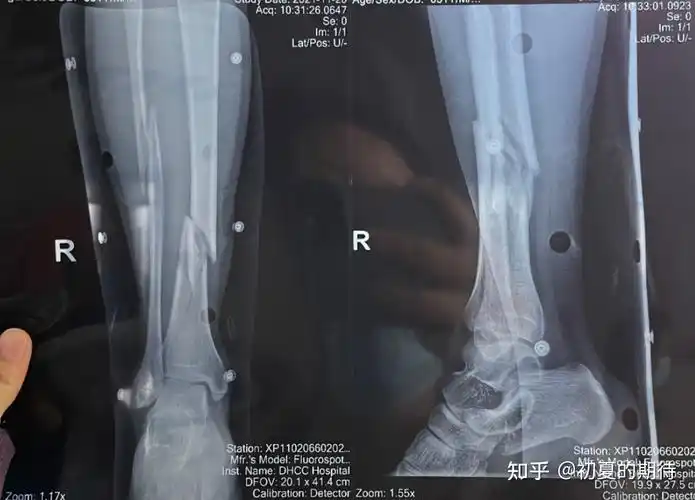

2014-07-20 于永军 医师 工伤右下胫联合分离术 韧带重建,右小腿肌肉

受伤时ct检查

这种疼痛不是一般人能承受的,并且ct检查的医生还把我的右小腿断口位